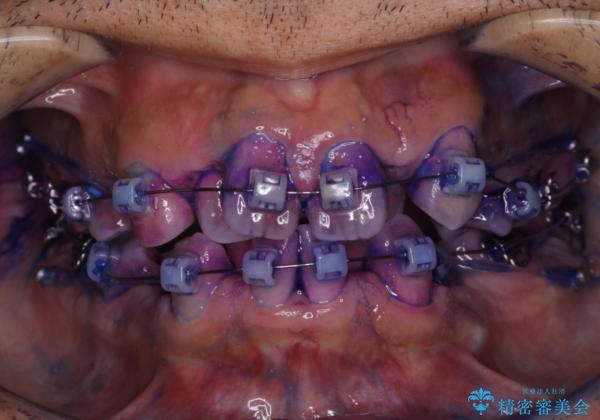

- ワイヤー装置で矯正中の方です。歯磨きがしずらく、専門的な機械でクリーニングしてほしいとの事でした。PMTC60分コースを行いました。

ワイヤー矯正中はブラッシングが難しくなるため、磨き残しが多くなることがあります。適切な道具を使って、適切なブラッシング方法を習得することで、磨き残しを減らすことができます。

また、矯正で歯の移動があると今までなかったところに隙間が出てきたり、ガタつきが解消されてきたりすることで、お口の中の環境が変わります。

矯正治療中も清潔な口腔内を保つことは、とても大切です。そのため、定期的に専門的な機械・材料を使用したProfessinnalcleaning(pmtc)を行うことがおススメです。